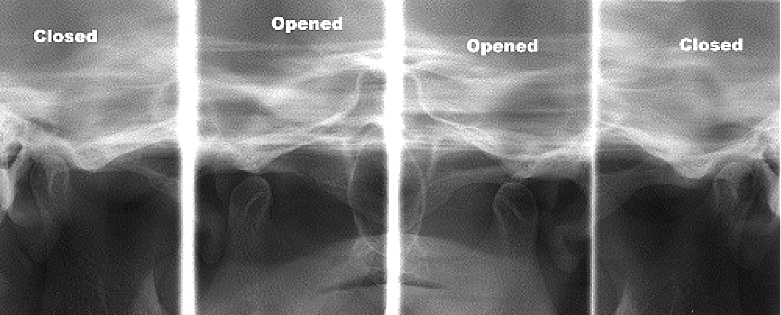

c. 턱뼈 및 턱관절의 상태

추가로, 이를 둘러싼 뼈의 밀도와 높이를

평가하는 데 도움을 주는데요.

이는 자연치의 안정성을 판단하고,

발치나 임플란트 시술 등의

치료 계획 수립에 중요한 근거로 사용됩니다.

더불어,

턱관절의 구조적 이상이나

초기 관절염, 마모 등도 진단할 수 있어,

추가적인 물리치료나 관리 방안을

마련할 수 있습니다.